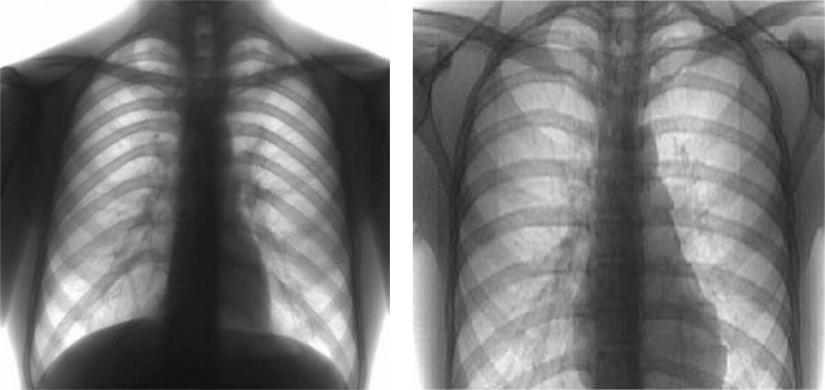

Рентгеновские снимки при врожденной эмфиземе легкого

Раздел: Визуальные уроки